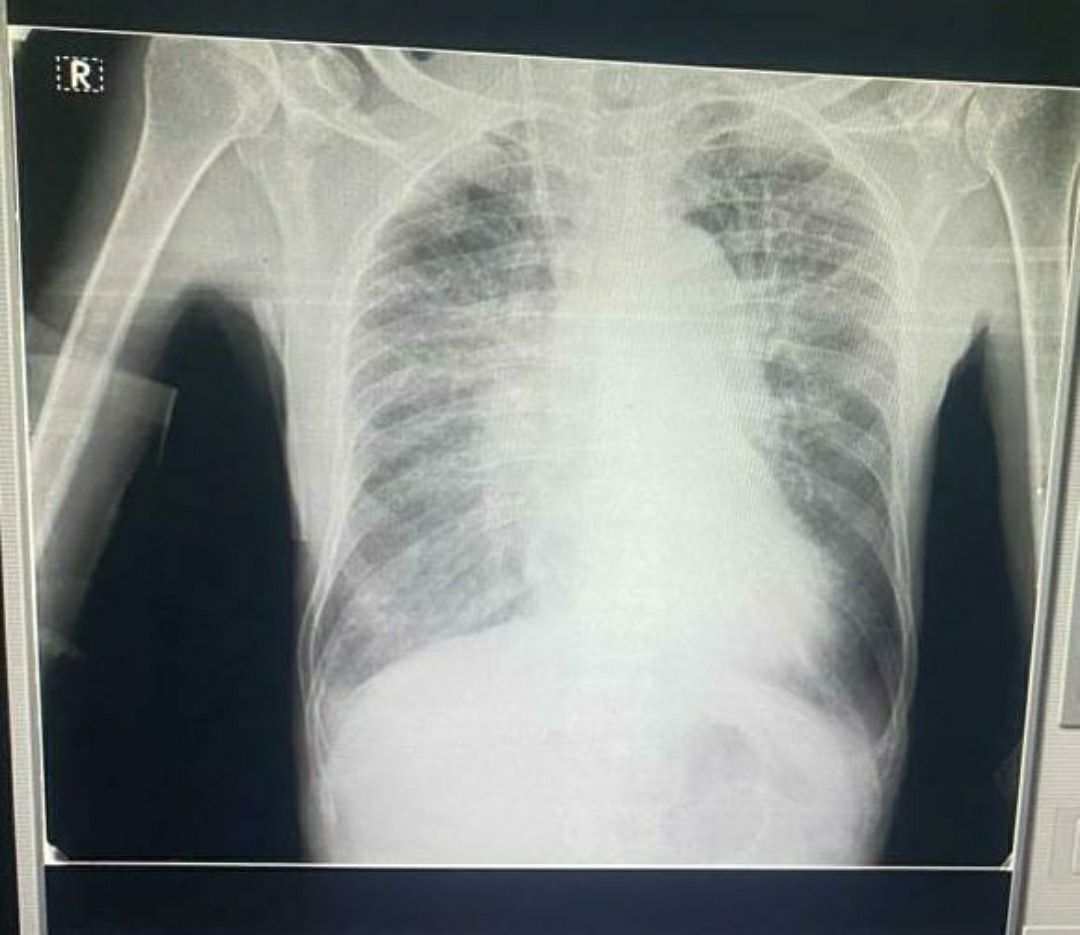

RS-BAE+,Diffuse wheeze+, Rt IMA,ICA crepts +,decreased breath sounds B/L.

DIAGNOSIS:AKI on CKD secondary to Right middle lobe consolidation.